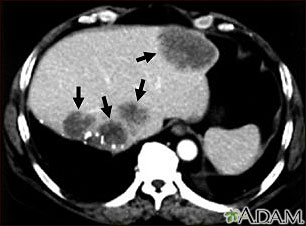

- CT scan of the abdomen